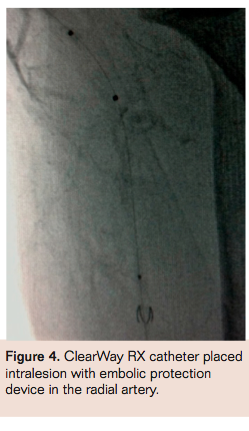

A 7 Fr 90 cm Flexor Shuttle guiding sheath (Cook Medical) was advanced into the distal axillary artery from a right femoral approach. The patient received IV unfractionated heparin for anticoagulation. A ViperWire with a 0.017˝ tip (CSI) was advanced into the radial artery. Then an Emboshield NAV6 filter (Abbott Vascular) was advanced and deployed to the proximal radial artery. Super selective delivery of 10 mg of tPA, weight-adjusted eptifibatide (15.8 mg), 200 mcg nitroglycerin, and 2.5 mg verapamil were delivered to the distal brachial artery via a 3 mm x 20 mm ClearWay RX catheter (Atrium Medical) placed at the site of the main thrombus (Figure 4). After 10 minutes, angiography demonstrated minimally improved thrombus burden, but now with contiguous slow flow via the brachial to radial artery. Ulnar flow remained absent. Rheolytic thrombectomy with a 4 Fr AngioJet (Bayer HealthCare) was then performed with four passes from the distal brachial artery to the proximal radial artery. With each RT pass, the retained contrast within the thrombus visually improved.